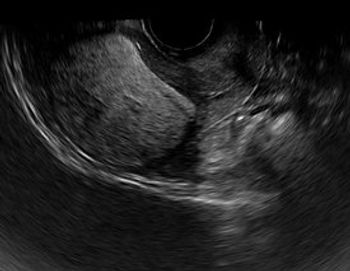

Sagittal image from a transvaginal sonogram in a patient with bleeding after a spontaneous abortion. The endometrium (between cursors) was thick and heterogeneous, measuring 8.5 mm in thickness (Fig1). Color doppler image in same patient shows focal flow (Fig. 2 - arrow) within the heterogeneous endometrium.